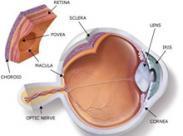

眶假瘤

628健康網(wǎng)為您分享有關(guān)眶假瘤的癥狀,眶假瘤的治療方法,眶假瘤的預(yù)防知識(shí),眶假瘤的癥狀圖片,眶假瘤吃什么藥,眶假瘤怎么治...